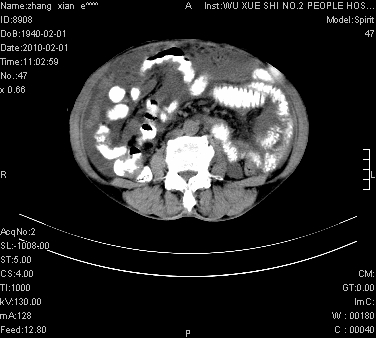

标题: CT24434:70岁 女 腹胀,腹水原因待查 [打印本页]

标题: CT24434:70岁 女 腹胀,腹水原因待查

大量腹水,脾脏囊性占位,子宫颈占位,右侧腹股沟淋巴结肿大,建议+c,先查妇科。

腹盆腔大量积液,子宫增大,子宫颈增大外形不规则,内见低密度影,膀胱后壁显示不清,右腹股沟肿大淋巴结,脾脏囊性占位,子宫颈占位,子宫颈癌?建议增强。

子宫、宫颈占位?转移性腹水?肝性腹水?脾脏囊性占位,囊肿?血管瘤?淋巴瘤?

考虑:1、腹膜转移,大量腹水;

2、脾占位性病变;

3、左侧卵巢占位性病变,建议增强进一步检查。

大量腹水,右肾、脾囊肿可能性大          考虑左侧附件区占位,建议增强